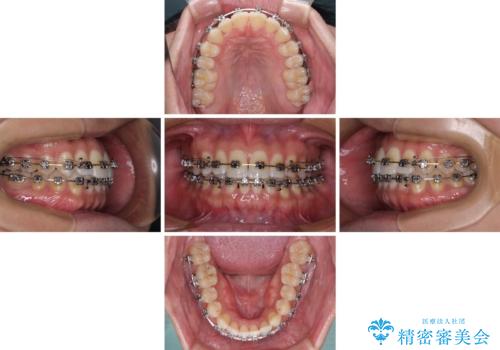

【モニター】楽して治したい メタルブラケットによる矯正治療

- メタルブラケット

- 1年4ヶ月

- 前歯のデコボコを気にして来院された患者様です。

インビザラインによるマウスピース矯正も適用となる歯列でしたが、できる限り自己管理の煩わしさのない状態で治したいとのことで、ワイヤー装置にて矯正治療を行うこととしました。

予定していた期間より長くかかりましたが、1年強できれいな歯列に仕上がりました。